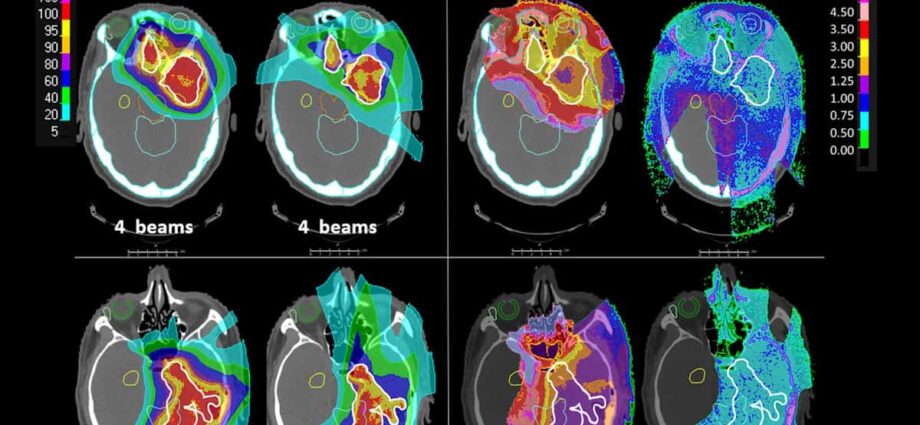

La terapia protonica clinica convenzionale utilizza una serie di picchi per irradiare il volume del tumore. La tecnica shoot-through, d’altra parte, impiega fasci di protoni ad alta energia che viaggiano direttamente attraverso il paziente, depositando la dose lungo tutto il loro percorso, con i picchi posizionati all’esterno del corpo.

Le radiazioni shoot-through hanno fornito una copertura del bersaglio paragonabile a IMPT originali e hanno raggiunto lo stesso numero di obiettivi clinici. Le dosi di molti organi a rischio, tra cui il tronco encefalico, l’ippocampo, l’ipofisi e i nervi ottici, erano più basse nello shoot-through rispetto a IMPT.

Questa dimostra come le distribuzioni di dose per i fasci di protoni shoot-through siano meno dipendenti dai tessuti che attraversano. Ciò è particolarmente importante per i pazienti con tumori cerebrali, spiegano i ricercatori, poiché i tumori vicini ai seni paranasali e alle cavità potrebbero essere considerati non idonei per la terapia protonica, a causa di cambiamenti nel riempimento del seno mascellare o della necessità di imaging e adattamento che richiedono tempo.

Per gentile concessione di: CC BY 4.0/Phys. Med. Biol. 10.1088/1361-6560/ad0280)